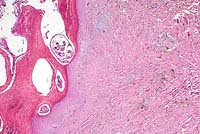

Case 9-1. Skin. Well-differentiated eosinophils clustered in a dilated venule and infiltrating the dermis. 40X

AFIP Diagnosis: Haired skin, dermis and subcutis: Eosinophil infiltrate, severe, with fibrosis and fewer lymphocytes, plasma cells, mast cells and neutrophils, New Zealand white rabbit, lagomorph.

Conference Note: Although the contributor's diagnosis was carefully considered, and it is agreed that the submitted case resembles that reported by Perkins et al., it was concluded that the nature of the process represented in the skin sections is uncertain. Since the infiltrate does not contain atypical cells, blasts or immature myeloid cells, a reactive lesion cannot be excluded. Possible causes include hypersensitivity, parasites, drugs and non-eosinophil neoplasia.